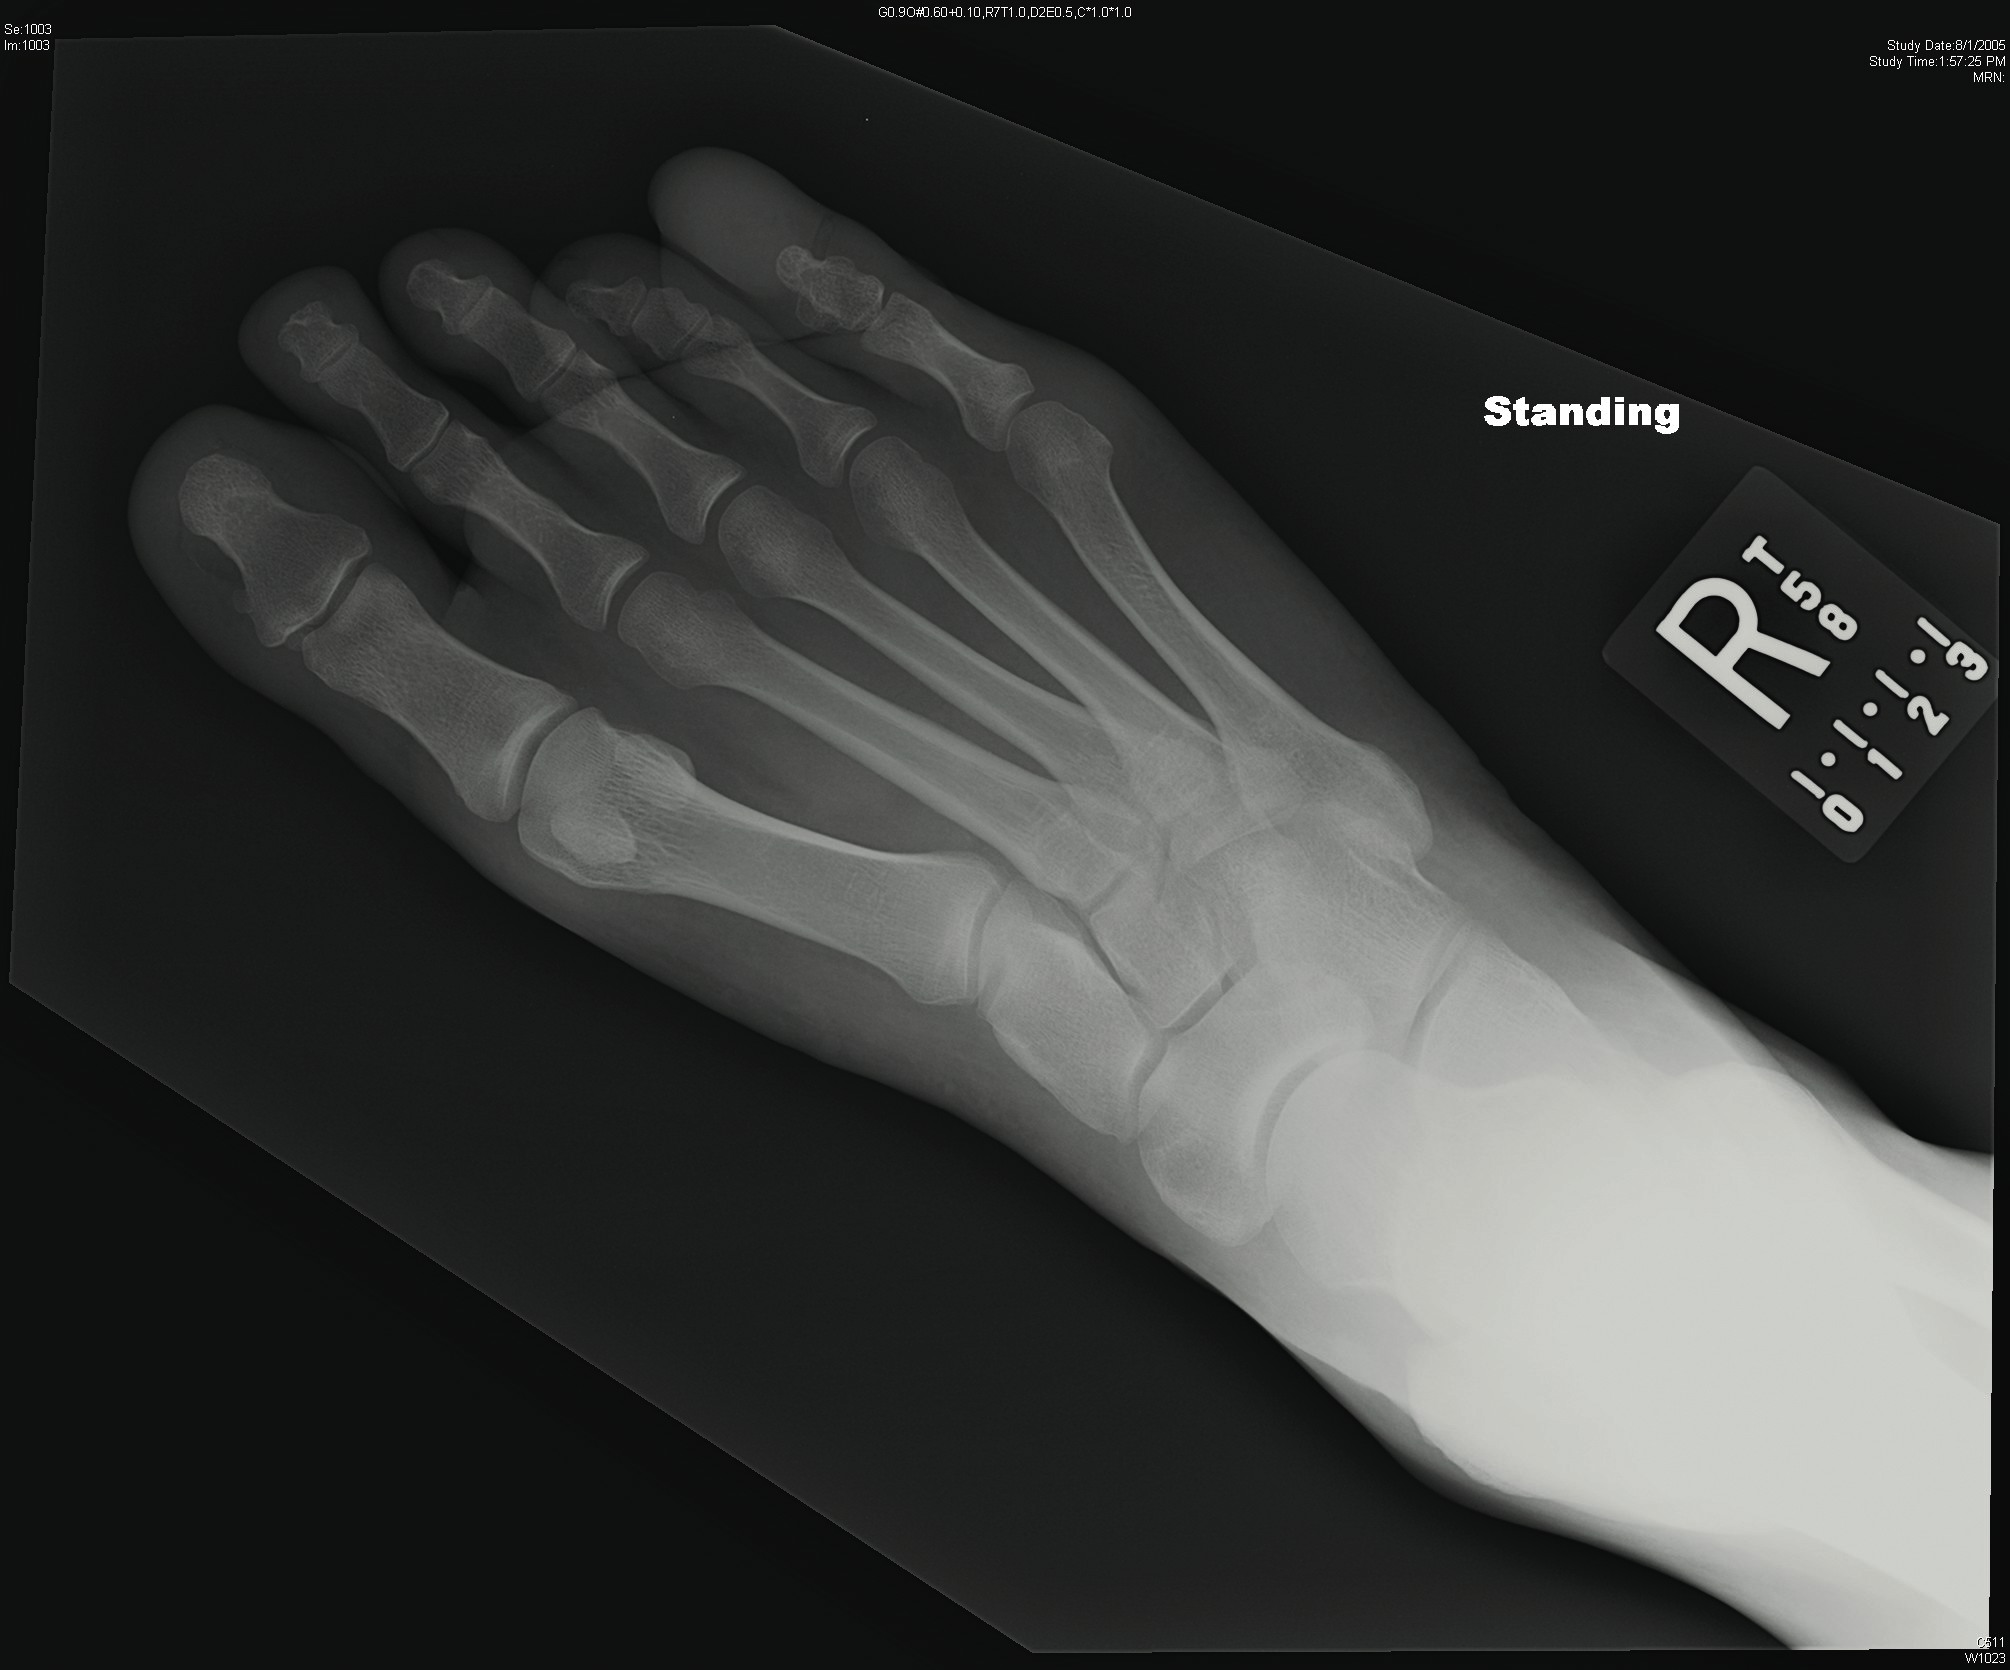

Case Study: When A Slow Growing Mass Suddenly Causes Adjacent Toe Pain

A 30-year-old male presented to clinic with a complaint of a slowly growing mass of the right fifth toe since childhood. The mass recently began to cause adjacent toe pain and the patient requested removal of the mass for this reason. The patient’s past medical history was unremarkable and his exam was notable for a large mass to the distal right fifth toe with subtle duplication of the distal phalanx. The patient underwent excision of the mass with a concomitant distal Syme’s amputation of the toe. The histologic analysis identified the mass as a benign collagenoma. The patient was referred to endocrinology due to a high association of collagenomas with multiple endocrine neoplasia type -1 (MEN1).10 Additional workup determined this was a solitary tumor without evidence of MEN1. The patient recovered from the procedure without incident and has had no recurrence of his neoplasm.